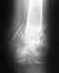

2.Снимок не представлен, поэтому невозможно сказать, есть ли преимущества абстрактной пластины перед другими вариантами фиксации

в этой конкретной ситуации. Может быть, и нет.